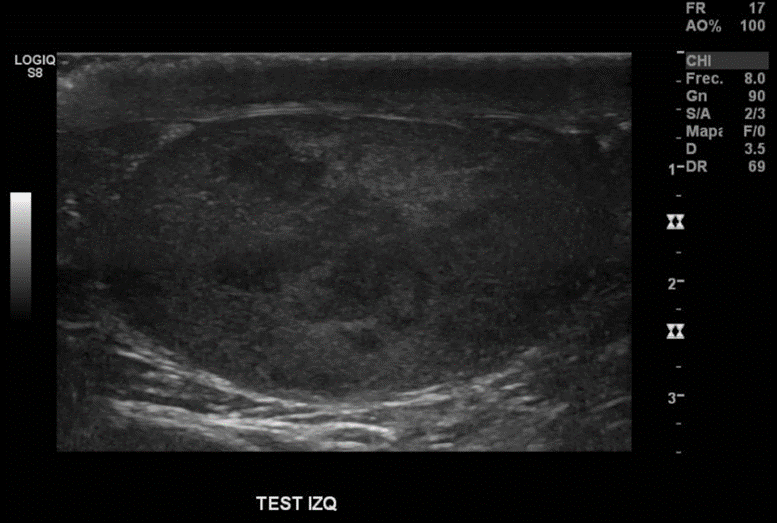

Descripción de hallazgos:

Testículo izquierdo heterogéneo, con áreas hipoecogénicas, tenue señal al Doppler, con imagen nodular hipoecogénica, heterogénea, con señal al Doppler, sugerente de neoplasia

Hallazgos: Testiculo derecho de tamaño, forma y estructura normal. Parénquima homogéneo sin lesiones nodulares El testículo izquierdo se observa aumentado de tamaño. Presenta alteración de la estructura de todo el parénquima con múltiples imágenes nodulares hipoecogénicas vascularizadas que miden hasta 2 cm de diámetro En la cabeza del epididimo derecho se observa un quiste de 2,2 mm de diámetro. Epididimo izquierdo sin alteraciones No se observa hidrocele No se observa dilatación de los plexos pampiniformes.

Impresión Diagnóstica: Obs neoplasia testicular izquierda multifocal. Quiste epididimario derecho